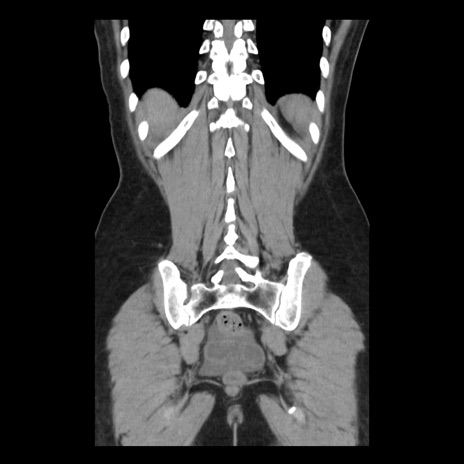

症例10(冠状断像)

【症例】 50歳代女性

【主訴】 腹痛

【現病歴】前日生レバーを食べた。今朝に排便あり。 昼前に突然発症の腹痛を生じ、当院救急外来を受診した。

【既往歴】 子宮筋腫にてで子宮全摘後

【身体所見】 意識清明、腹部:平坦、軟、下腹部やや左を中心に圧痛・反跳痛あり、筋性防御あり

【データ】WBC 7800、CRP 0.07